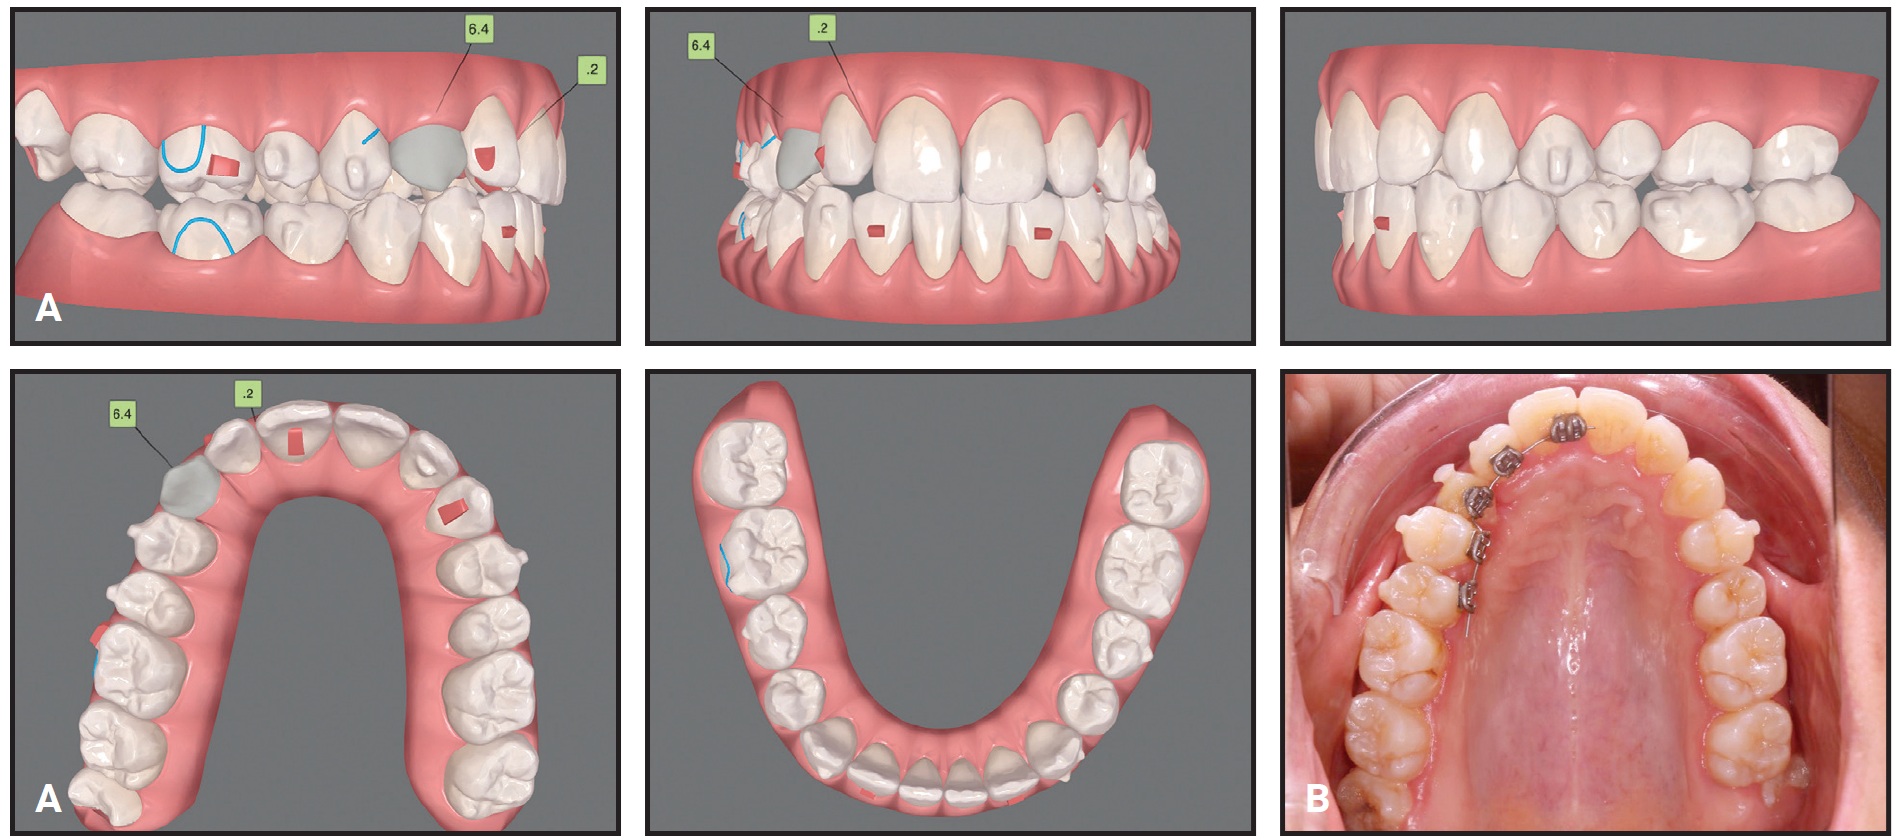

The treatment plan was divided into two stages (see box). The first, involving arch expansion and space preparation for the canine, would require 44 sets of aligners, changed weekly. In the second stage, which would involve 32 sets of aligners changed every two weeks, the canine would be exposed, and traction would be performed.

The first set of aligners was designed to expand the maxillary arch and prepare space for the upper premolars with sequential molar distalization (Fig. 8). Class II elastics (3⁄16", 4.5oz) were worn from the first premolars to the lower molars to prevent labial movement of the premolars. Next, the premolars were derotated and moved buccally into the arch. Using the contralateral canine’s mesiodistal width as a guide, about 7.5mm of space was prepared for the impacted canine.

Fig. 8 Case 2. ClinCheck plan of first treatment stage, involving expansion of maxillary arch and preparation of space for impacted canine.

After two months, the canine was surgically exposed. A button was bonded to the labial side of the upper right first molar, and elastic thread was used to apply a distobuccal force vector, with the primary objective of moving the canine away from the incisor roots.

After the first stage of treatment, the canine was partially visible and had moved buccally into the arch. Because 30° of derotation would be required for alignment, in addition to extrusion and buccal root-torquing movements, a lingual fixed appliance would be used as an auxiliary; the ClinCheck* plan was modified accordingly (Fig. 9). Lingual .022" Victory** lower-incisor twin brackets were bonded from the upper right central incisor to the second premolar, and an .016" nickel titanium lingual archwire was engaged to correct the rotation. At the same time, clear aligners were used to extrude the upper right canine, with elastics (3⁄16", 3.5oz) worn from the canine hook to cutouts on the labial sides of the canine and first premolar.

Fig. 9 Case 2. A. ClinCheck plan of first refinement stage, showing modifications to account for use of sectional fixed appliance on lingual side of upper right segment. B. Fixed lingual appliance used as auxiliary during first refinement stage.

Four months later, buccal root torque was applied to the canine with an .016" × .022" rectangular TMA*** lingual archwire. During the detailing phase, the fixed lingual appliance was removed, and treatment continued with 12 sets of clear aligners, changed weekly. To reduce the visibility of the attachments, they were placed on the lingual sides of all upper anterior teeth except the right canine.